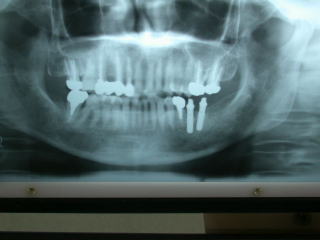

1枚目写真はインプラントの例です。

●インプラントのレントゲン写真例